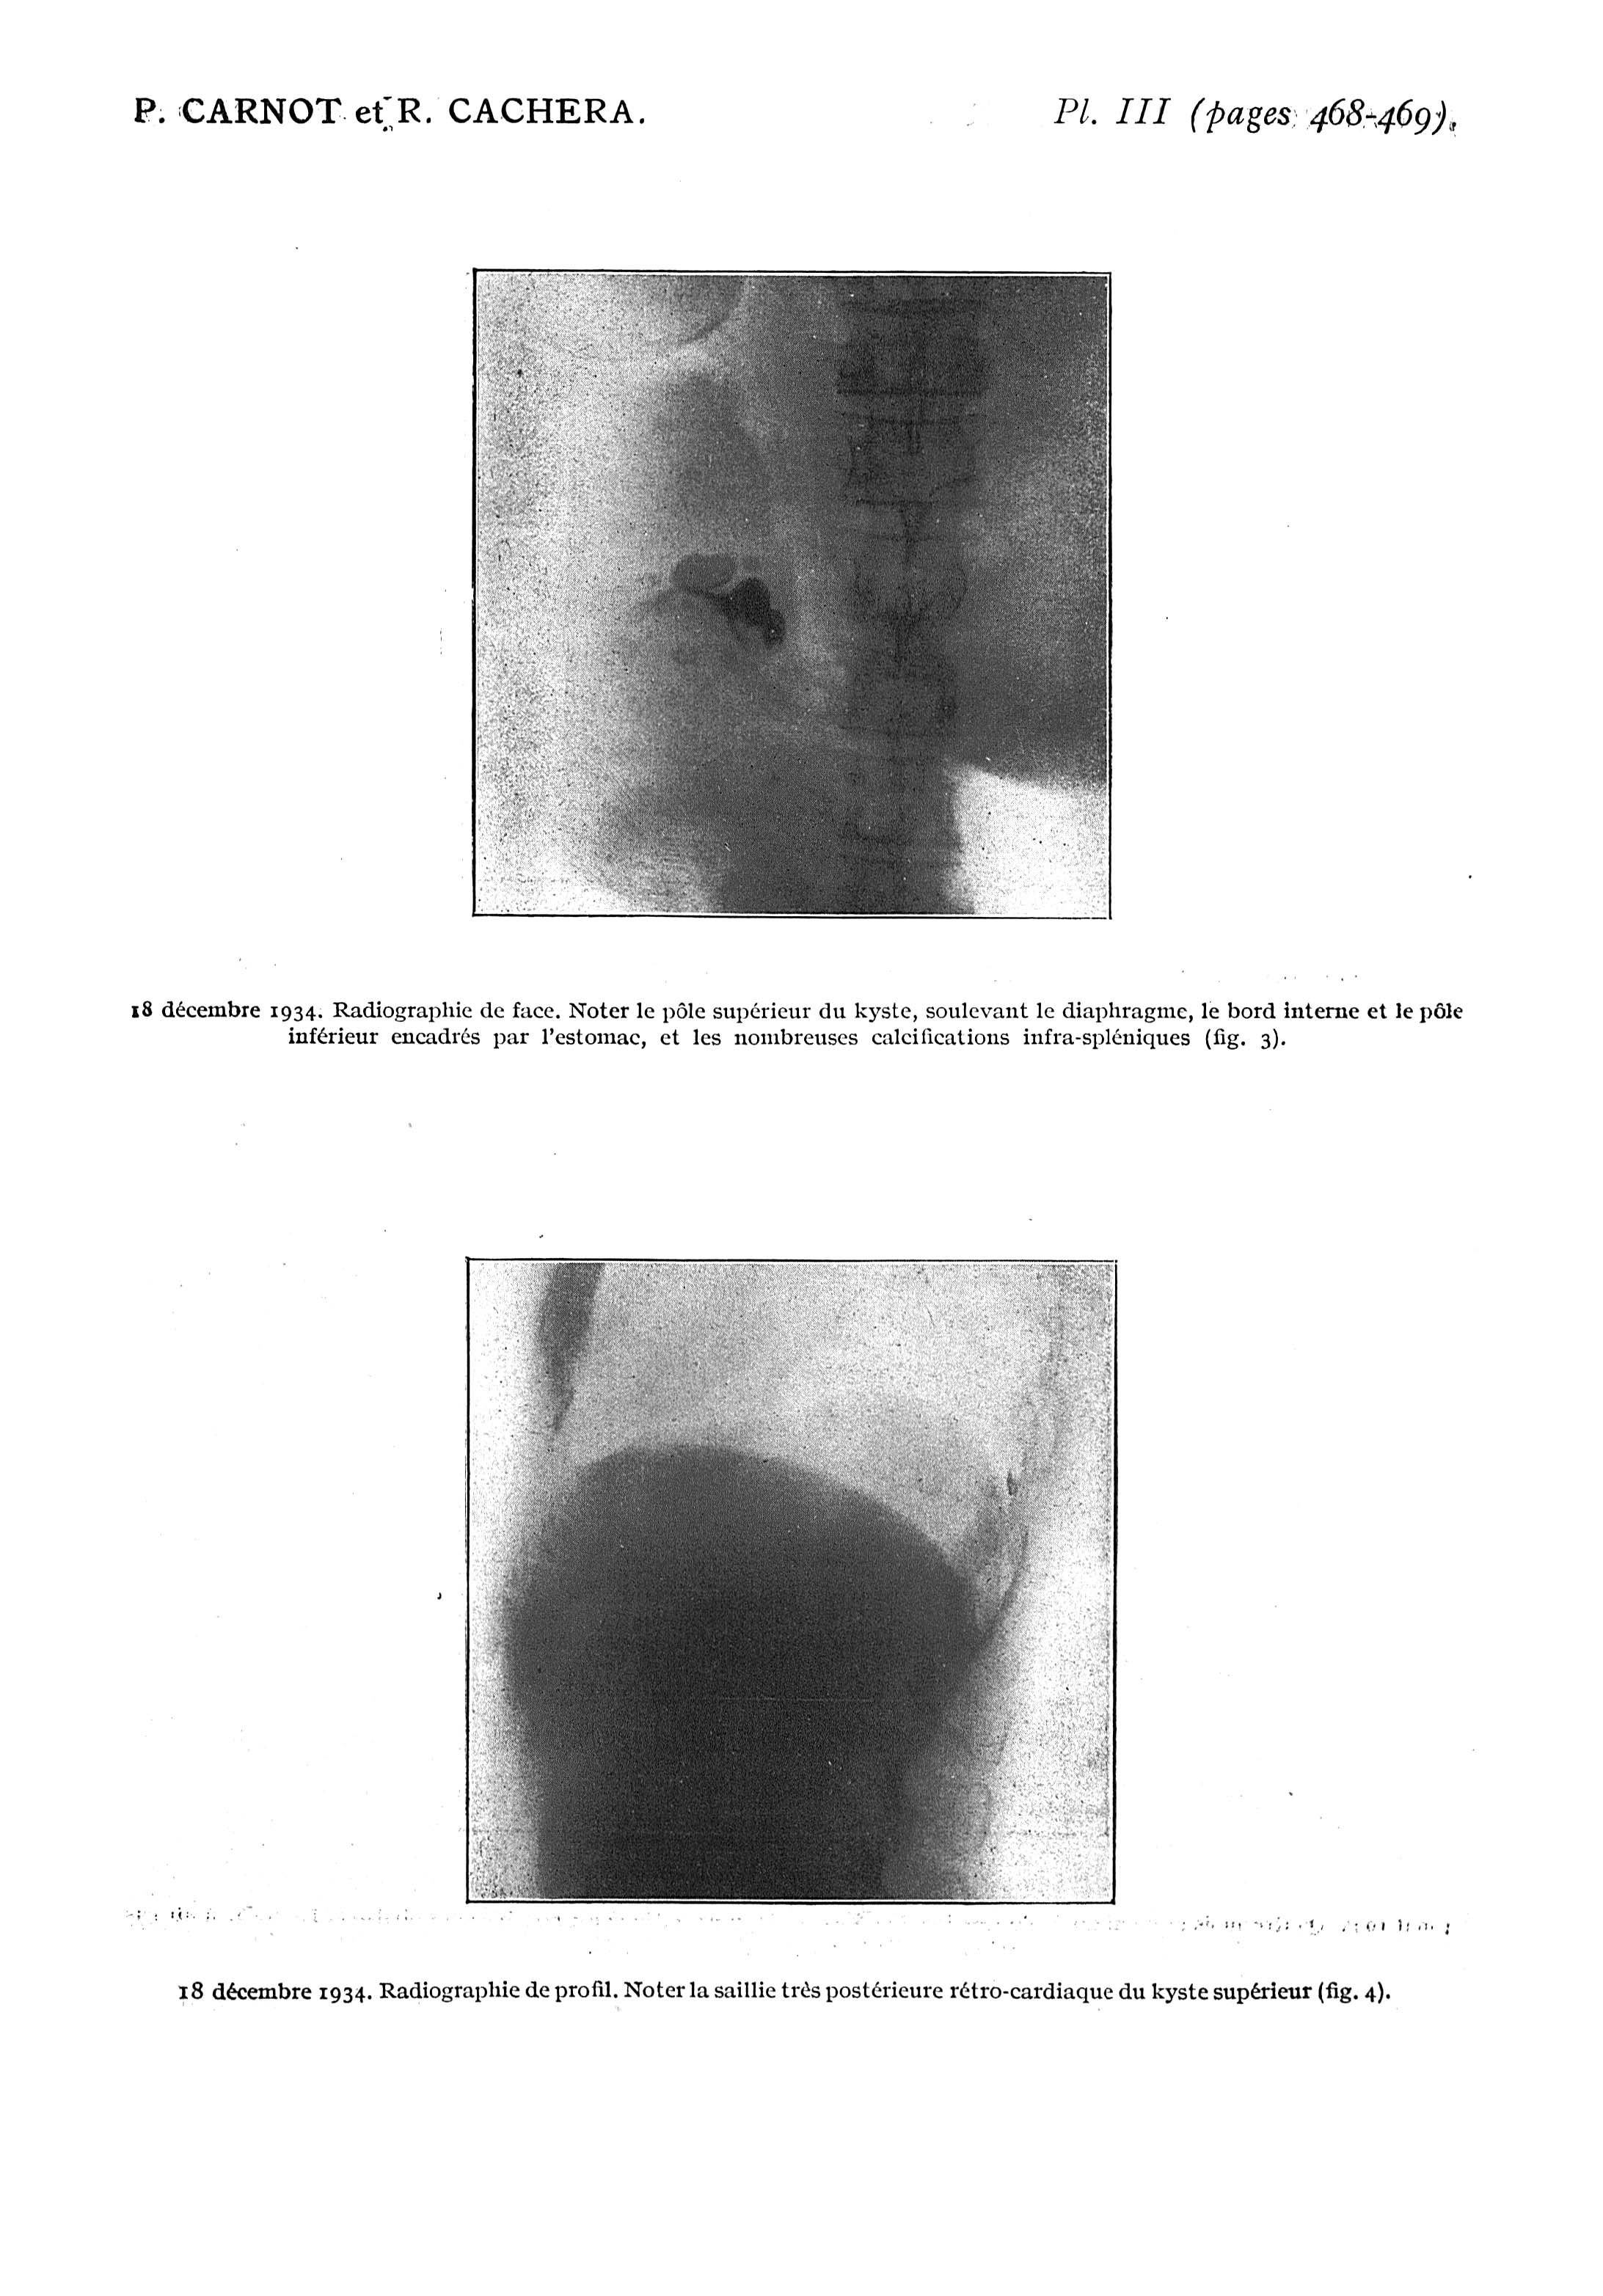

Fig. 3. - 18 décembre 1934. Radiographie de face / Fig. 4. - 18 décembre 1934. Radiographie de profil - Paris médical : la semaine du clinicien